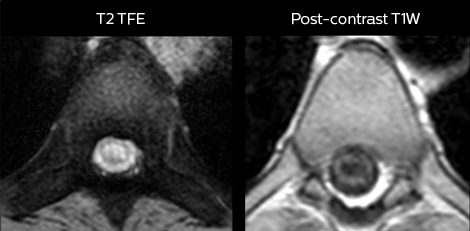

„Mit mDIXON TSE-Sequenzen ist es dank der T2-gewichteten Bilder auf Wasserbasis aus derselben Erfassung möglich, gleichzeitig morphologische Veränderungen aus den T2-gewichteten In-Phase-Bildern zu charakterisieren und ödematöse Veränderungen darzustellen. Auf diese Weise können anatomische und morphologische Befunde wie eine partielle oder komplette Bandruptur, ein knöcherner Ausriss oder ein Hämatom abgeklärt werden.“ „In Bezug auf die Beurteilung von Weichteilgewebe bietet mDIXON ähnliche Vorteile. Bei einer T2-gewichteten mDIXON TSE-Erfassung helfen die multiplen Kontraste zum Beispiel bei der Abklärung von pathologischen Befunden in Faserbündeln der peripheren Nerven, die auf anatomischen oder entzündlichen Veränderungen beruhen können.“ „Bei peripheren Gelenken erhalten wir mit mDIXON TSE eine gute Qualität in diffizilen Bereichen. Bilder mit Fettsuppression erscheinen vollständig homogen, auch bei einer großen Abdeckung mit 3,0 T – zum Beispiel beim Schulter- oder Beckengürtel – bzw. in den Gelenkflächen oder um Metallprothesen herum*, wo eine Fettsuppression mit STIR oder spektraler Suppression häufig unzureichend ist und zu Schwierigkeiten bei der Diagnose führt. Wenn ein diagnostisches Bild auf Anhieb richtig dargestellt wird, ist es nicht nötig, eine Sequenz zu wiederholen oder hinzuzufügen.“ „Mit mDIXON TSE-Sequenzen ist es dank der T2-gewichteten Bilder auf Wasserbasis aus derselben Erfassung möglich, gleichzeitig morphologische Veränderungen aus den T2-gewichteten In-Phase-Bildern zu charakterisieren und ödematöse Veränderungen darzustellen. Auf diese Weise können anatomische und morphologische Befunde wie eine partielle oder komplette Bandruptur, ein knöcherner Ausriss oder ein Hämatom abgeklärt werden.“ „In Bezug auf die Beurteilung von Weichteilgewebe bietet mDIXON ähnliche Vorteile. Bei einer T2-gewichteten mDIXON TSE-Erfassung helfen die multiplen Kontraste zum Beispiel bei der Abklärung von pathologischen Befunden in Faserbündeln der peripheren Nerven, die auf anatomischen oder entzündlichen Veränderungen beruhen können.“